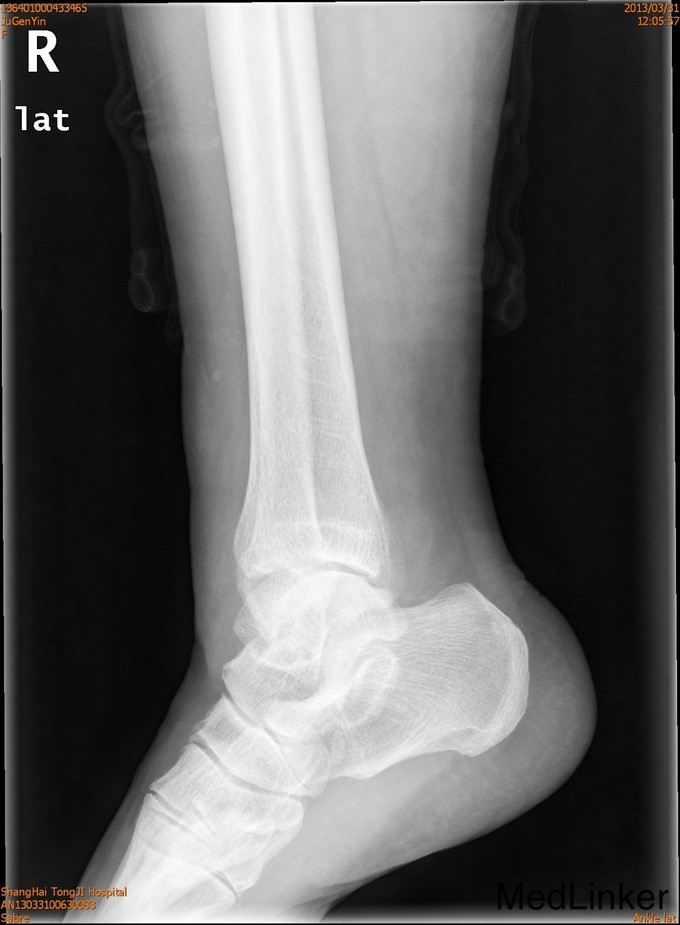

患者女,61岁,摔伤后右踝足肿痛4天。患者4天前不慎摔伤,即感右足踝疼痛,肿胀,活动受限 ,休息后疼痛减轻,X线示右外踝骨折。

查体:一般情况可,右外踝肿胀,淤青,压痛明显,可及骨擦感,足部活动感觉可。

诊断为右外踝骨折,完善术前检查后于全麻下行右外踝骨折ORIF术+距腓前韧带修复术。